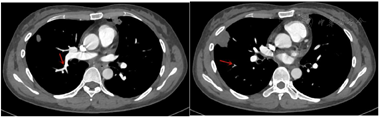

入院后出现胸痛症状加重,查D2聚体进行性升高,心肌酶正常,2020.12.29肺动脉造影(CTPA)提示左肺部分肺动脉分支充盈缺损,双侧上、下肢静脉彩超未见确切异常,诊断为急性肺栓塞,予以低分子肝素抗凝,随后免疫性结果回示抗nRNP/Sm抗体(+++),抗Sm抗体(++),抗SSA抗体(+),抗细胞周期抗体(++),抗核小体抗体(+),抗组蛋白抗体(+),抗核抗体(+)滴度1:3200,抗双链DNA抗体171.01 IU/mL,风湿科会诊后以"结缔组织疾病,抗磷脂综合征"转风湿免疫科进一步诊治。转入后复查HGB 54 g/L,血D-二聚体8.89 mg/L FEU,呈进行性升高趋势,直接抗人球蛋白实验阳性,抗甲状腺球蛋白抗体(anti-Tg)136.75 IU/mL,抗甲状腺过氧化物酶(anti-TPO)129.48 IU/mL。骨髓细胞学涂片、流式细胞术、活检等结果无确切血液系统肿瘤依据。CTPA结果提示右肺上叶尖段肺动脉起始部、右肺下叶前基底段、外基底段肺动脉内肺动脉栓塞,下叶为完全性栓塞(图1)。

4个月后门诊复查CTPA结果提示血栓病灶较前明显缩小,无新发血栓征象(图2)。考虑患者存在多种免疫介导疾病,建议终身口服华法林抗凝,监测INR(2-3),定期呼吸科与风湿科随访。